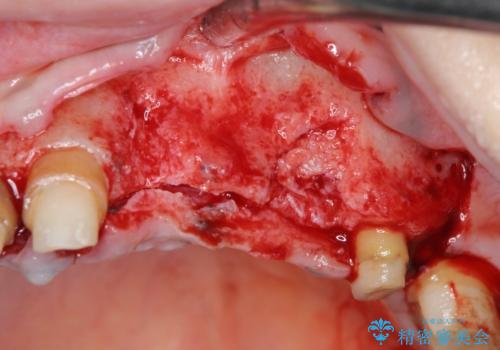

抜去を行ったのち、インプラント治療を計画しますが骨量が少ないため、まず骨の造成を行ったのちインプラントを埋入していく治療計画としました。